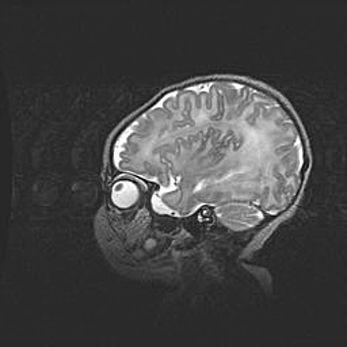

Аномалия Денди-Уокера. Признаки гипоплазии мозолистого тела.

Возраст: 5 месяцев 3 дня

Вес: 5550 г

Пол: мужской

Окружность головы: 39 см

Срок гестации: 40 недель

Аномалия Денди-Уокера – это порок развития головного мозга, для которого характерна триада симптомов: гипотрофия или аплазия червя мозжечка и/или полушарий мозжечка, расширение четвёртого желудочка с формированием ликворной кисты задней черепной ямки, гипертензионная гидроцефалия различной степени.

Гипоплазия мозолистого тела относится к дефектам внутриутробного этапа развития мозговой ткани, возникающим в процессе закладки структур головного мозга, что происходит на начальных этапах развития эмбриона.